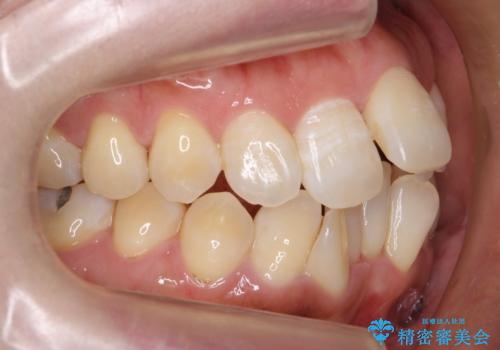

- 前歯の重なりを主訴に来院。

前歯が顔の真ん中に飛び出しているような状態でした。

右上の犬歯が奥深く埋伏していました。

右上以外の3本を抜歯しきちんと並べました。

前歯も引っ込み、口が閉じやすくなりました。